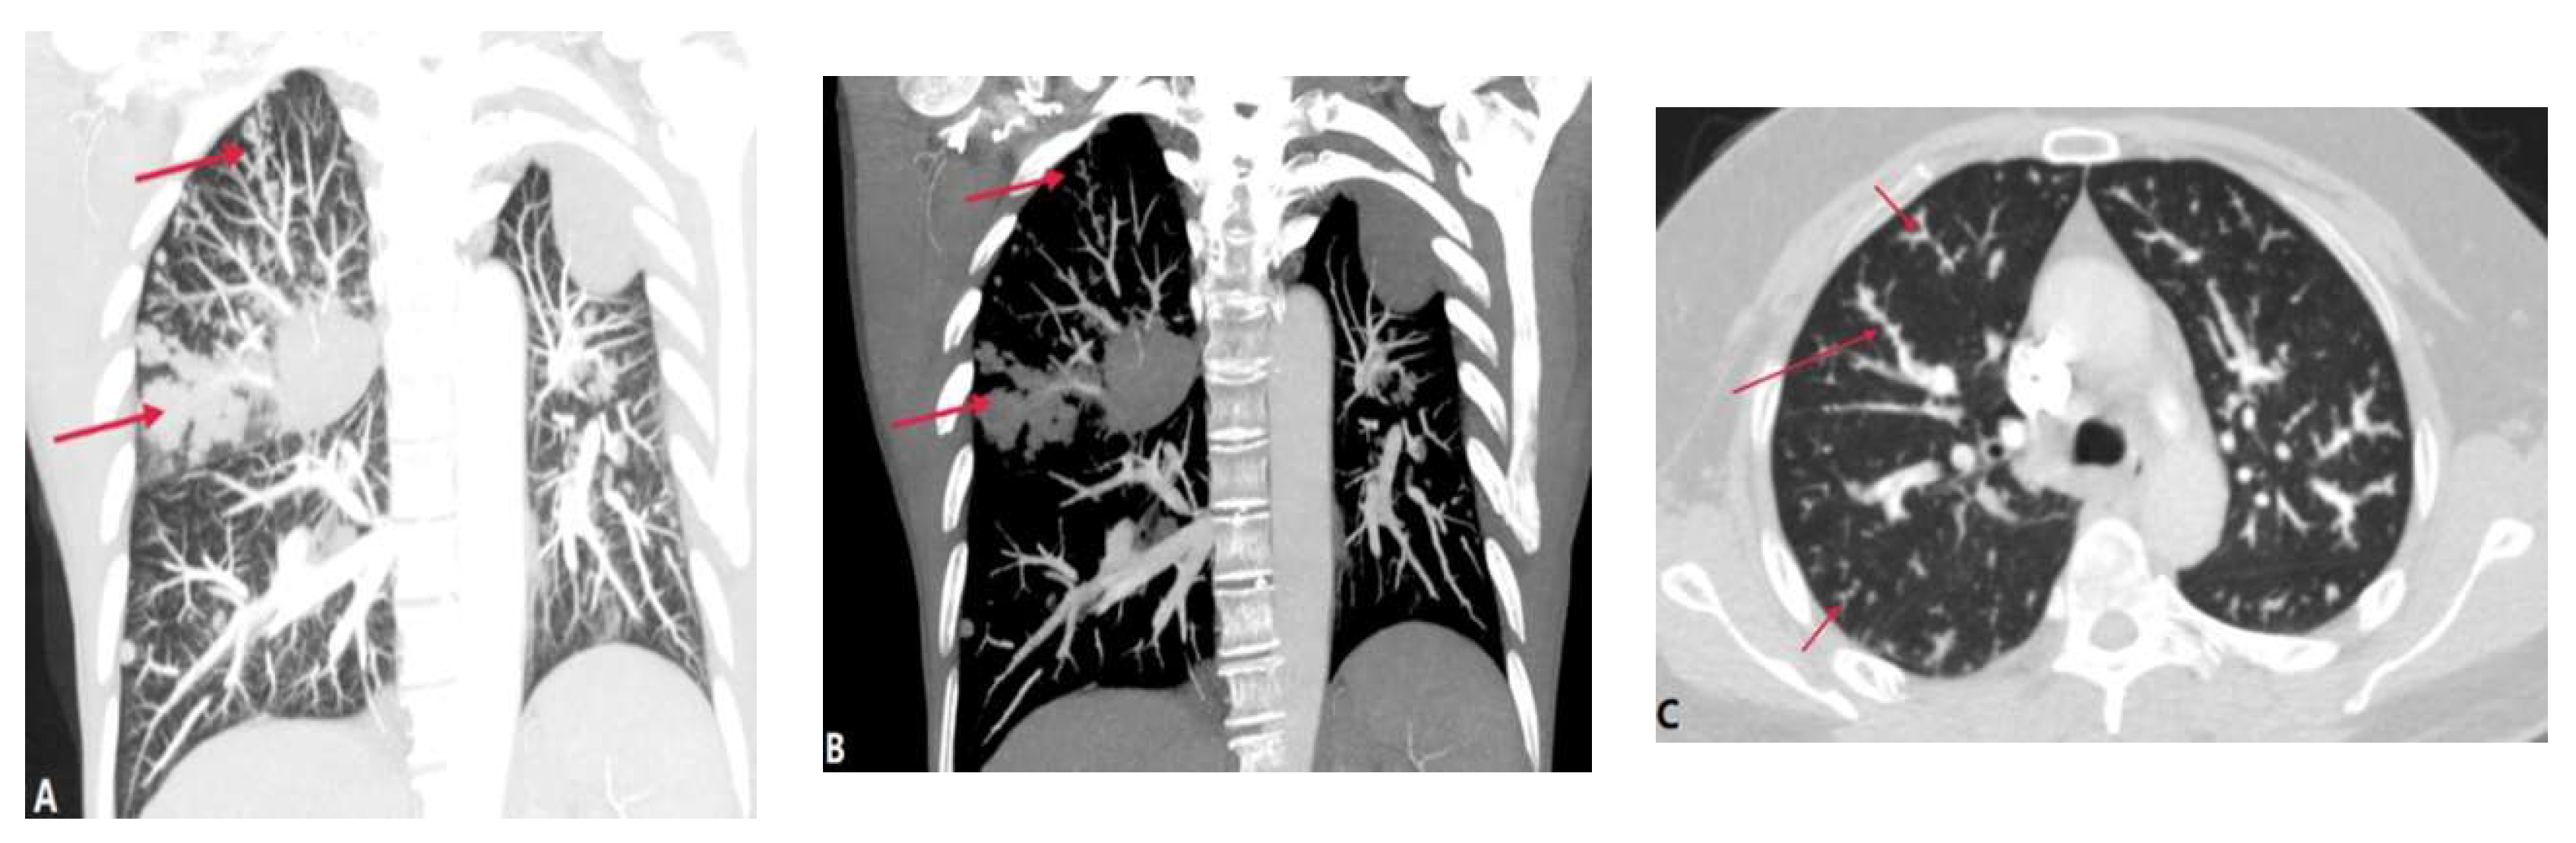

3.1.4. Septic Pulmonary Embolism (SPE)

3.1.5. Pulmonary Embolism caused by Foreign Bodies